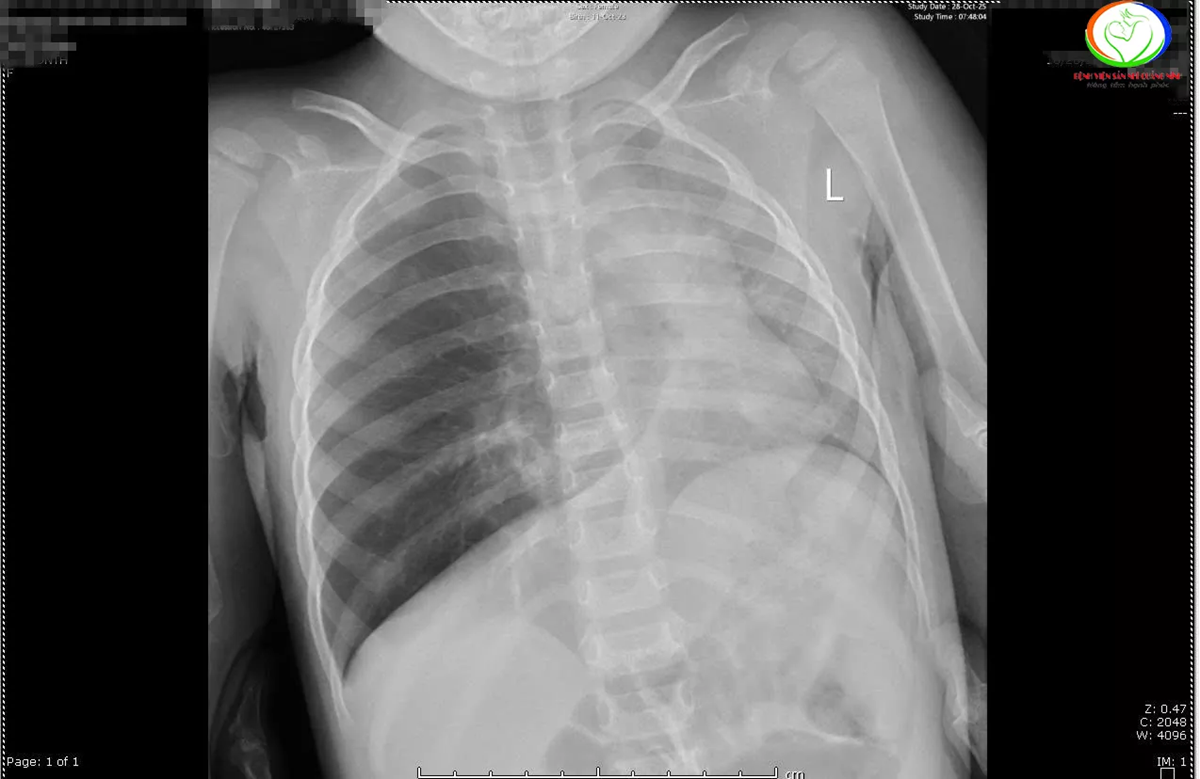

Kết quả chụp X-quang cho thấy các trẻ có hình ảnh ứ khí, mờ quanh rốn phổi. Riêng bệnh nhi N.N.L phổi trái giảm thể tích, kém sáng, xẹp phổi dạng dài thùy dưới phổi phải.